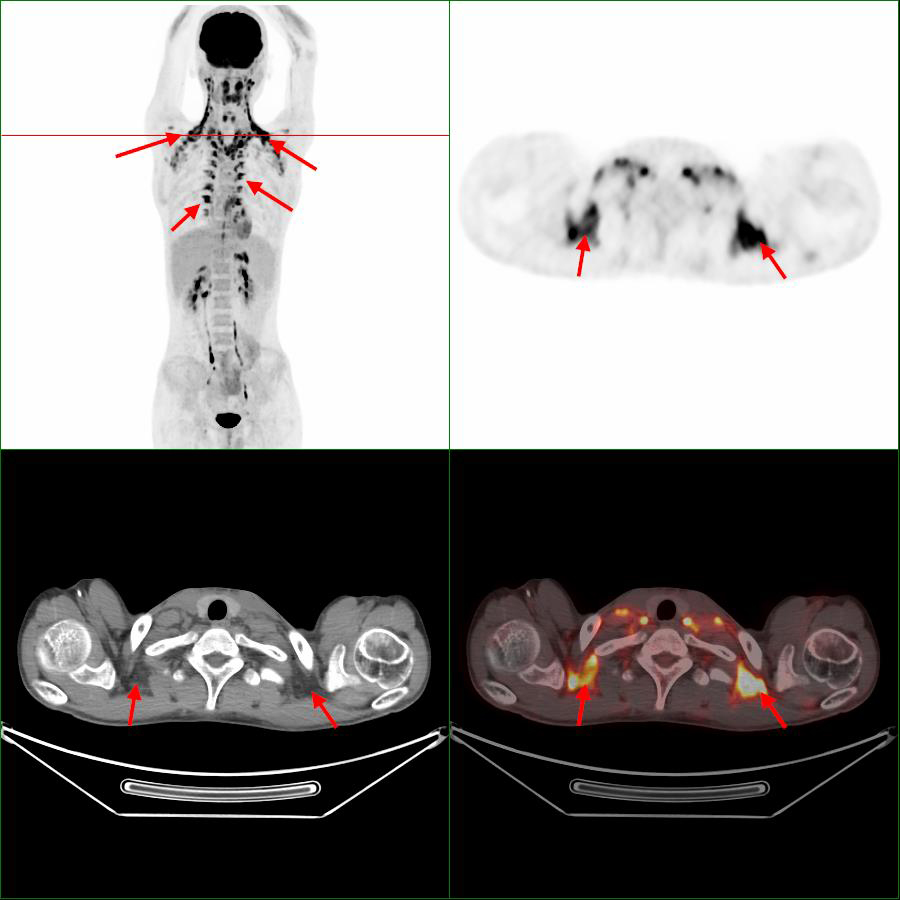

在寒冷環(huán)境下,人體為了維持體溫,棕色脂肪會迅速地分解和消耗,以釋放出能量來維持體溫,形成高代謝攝?。▓D1,箭頭),被PET/CT檢測到其顯影。對讀片醫(yī)生來說,它是偽影,會掩蓋該區(qū)域的病灶檢出,影響對病灶的判斷。當(dāng)對診斷有嚴(yán)重影響時,不得不改期再次進(jìn)行PET/CT檢查,造成不必要的時間和經(jīng)濟(jì)損失。

圖1 第1次顯像,箭頭指示為棕色脂肪顯影